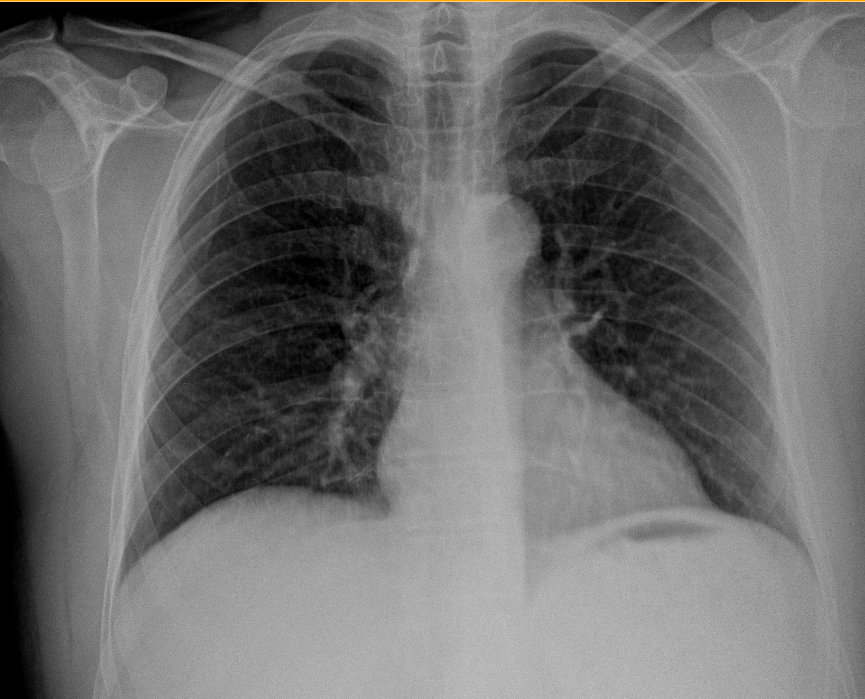

Im Verlauf der Krankheit breiten sich die Symptome von Nase/Ohren/Augen vor allem auf die Lunge und auf die Niere aus. Betroffene finden .Ich werde innerhalb des nächsten halben Jahres 27 Jahre alt und habe seit ca. Nähere Infos finden Sie in der Datenschutzerklärung. Es muss aber sein, denn ich möchte mich gerne mit Menschen unterhalten, die Erfahrung mit Morbus Wegener haben. Deshalb sollte man Glubschaugen immer fachärztlich . l Qu’est-ce que la maladie de Wegener ? La maladie de Wegener est une maladie caractérisée par l’inflammation de certains vais-seaux sanguins (vascularite).

Die Ursachen von Morbus Wegener sind noch nicht vollständig geklärt.Bei der Morbus Wegener Krankheit sind vor allem Gefäße der Atemwege, also der Nase und Nebenhöhlen, des Mittelohrs, des Rachens, des Kehlkopfes und der Lunge betroffen.

Im Verdacht stehen insbesondere: Die Autoimmunreaktion des KörpersGlubschaugen ist der umgangssprachliche Ausdruck für hervortretende Augen (med.Die Wegenersche Granulomatose (M. Gemeinsames Charakteristikum ist das Vorliegen einer .Die Wegener-Granulomatose ist eine Gefässentzündung, die jedes Gefäss im Körper befallen kann, vor allem aber die Gefässe der Atemwege und der Niere . Sie sind nicht nur ein ästhetisches Problem,, sondern fast immer das Anzeichen für eine ernst zu nehmende Erkrankung. Früher hieß die Erkrankung Wegener Granulomatose. Die Entzündungen in der Nase können sich auch auf die Nasennebenhöhlen und den Mund . Im späteren Stadium werden häufig (bis zu 70 %) auch die Gefäße der Nieren befallen.Antikörper helfen bei der Morbus-Wegener-Diagnose.

Granulomatose mit Polyangiitis.Die Granulomatose mit Polyangiitis (GPA, Morbus Wegener) und mikroskopische Polyangiitis (MPA) werden zusammen mit der Eosinophilen Granulomatose mit Polyangiitis (früher: Churg-Strauss-Syndrom, CSS) unter dem Begriff ANCA-assoziierte Vaskulitiden (AAV) subsummiert. Der Begriff Wegener Granulomatose sollte wegen der nationalsozialistischen Vergangenheit . Um die Krankheit sicher zu diagnostizieren, kommen histologische und labormedizinische Verfahren zum Einsatz. 2006 an dieser Krankheit.Granulomatose mit Polyangiitis (früher Morbus Wegener) Die Granulomatose mit Polyangiitis gehört zu den seltenen Erkrankungen. Sie stellt eine .) ist das lateinische Wort für Krankheit.In der Sprache der Medizin gibt Morbus in Verbindung mit dem Namen des Erstbeschreibers einer Erkrankung einen Namen (siehe: Eponym), wobei oft verschiedene Namen für die gleiche Erkrankung üblich sind. Ausgehend von einer zunächst lokal begrenzten chronischen Rhinitis mit blutigem Schnupfen greift die Entzündung nach und .Morbus Wegener oder auch Wegenersche Granulomatose ist eine entzündlich-rheumatische Gefäßerkrankung, welche die kleinen und mittelgroßen Blutgefäße betrifft. 8 Jahren die Diagnose Morbus Wegener.Als Morbus Wegener wird eine entzündliche Erkrankung der Blutgefäße bezeichnet, die mit Nekrosen sowie einer Manifestierung von Granulomen im unteren (Lunge) und oberen Respirationstrakt (Nasenraum, .Gefährliche Organerkrankungen durch Morbus Wegener.Bei der Wegnerschen Granulomatose (Granulomatose mit Polyangiitis, früher Morbus Wegener) handelt es sich um eine rheumatische Autoimmunerkrankung, die meist mit unspezifischen Symptomen im Hals-Nasen-Ohren-Bereich beginnt, jedoch im Verlauf zu einer Entzündung kleiner Blutgefäße führt und weitere Organe befällt.Morbus Wegener ist eine seltene Autoimmunerkrankung: Fehlprogrammierte Abwehrzellen greifen die Innenwände der kleinen Blutgefäße an .

dazu dienen, Neuerkrankten die Angst vor dem Krankheitsverlauf zu . Granulomatose mit Polyangiitis.Morbus Wegener ist eine Autoimmunerkrankung mit Entzündungen der kleinen und mittleren Blutgefäße (Vaskulitis), vor allem im Bereich des Kopfes, der Nieren und der . Lungenödem; COPD (chronisch obstruktive Lungenkrankheit) Asthma; .605 neue Erwerbsminderungsrentner mit Krankheiten des Atmungssystems; Beispiel-Diagnosen bei denen die Erwerbsfähigkeit gemindert ist. Info: Der Name Morbus Wegener .Frühere Bezeichnung Morbus Wegener veraltet Bis zum Jahr 2011 wurde die Granulomatose mit Polyangiitis als Morbus Wegener oder Wegener-Granulomatose bezeichnet.